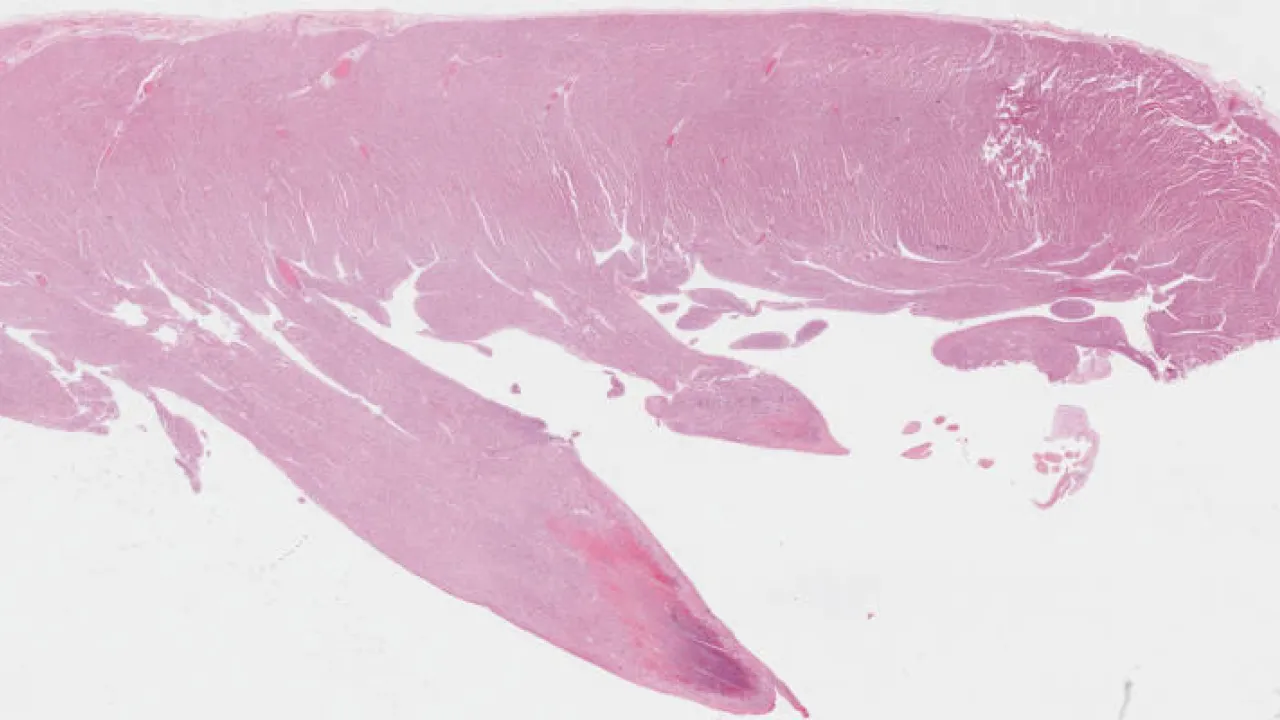

Heart, Myxoma, H&E stain

Heart, Myxoma, Movat's stain